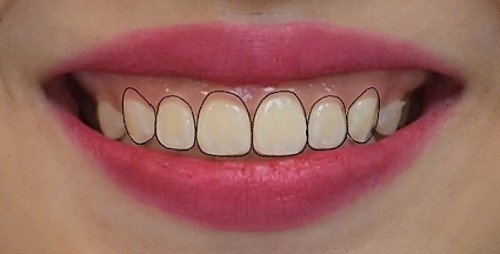

A 30-year-old female patient was referred to a private dental clinic seeking solutions for her gingival smile. The initial assessment encompassed a thorough clinical examination, photographic documentation, cone-beam computed tomography (CBCT) scans and impressions to collect essential data (see Fig. 1).

The length of the tooth crowns was clinically measured on the dental model (see Fig. 2), whereas the anatomical length was evaluated through CBCT images (see Figs 3 and 4). Based on the anatomical crown length, a smile design was created, and the patient was presented with a simulated smile before treatment (Figs 5 and 6). Upon approval of the simulated smile, a treatment plan was devised, establishing the future bone margin at 3-mm apical to the cementoenamel junction (CEJ) for each tooth, as indicated in Fig. 7.